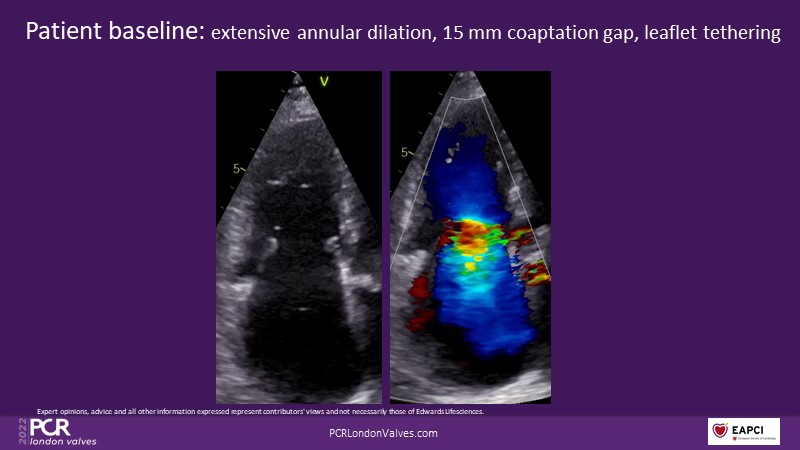

This innovative session takes you through the patient selection and anatomical characteristics when selecting amongst the different transcatheter options to treat tricuspid regurgitation, followed by a recorded demonstration using the PASCAL Precision repair system.

- To discuss the anatomical considerations that define suitable candidates for the different portfolio of options to treat tricuspid regurgitation